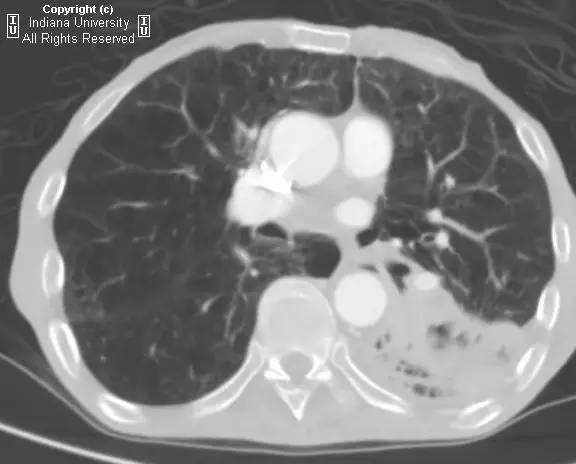

【病史】男性,咳嗽,体重减轻。

胸片示肺内高度膨胀性病变,膈肌扁平。左后胸部可见较大卵圆形不透亮区并液平面。CT示左肺下叶近后胸壁较大厚壁肿块并部分空洞形成,实性部分不均质强化。右肺下叶可见分叶状结节。左前下少量气胸。

【诊断】鳞状细胞肺癌并后部阻塞性肺炎